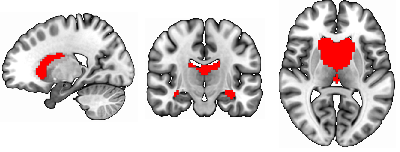

To identify the top ROIs for the intelligence prediction tasks, we first extracted the pooled ROIs after passing through the first layer of TopK Pool layer of a fully trained model using a holdout test set. We then selected the ROIs with highest frequency across each of the samples for all the intelligence scores. For fluid intelligence, we selected two ROIs (Middle Temporal Gyrus, and Middle Frontal Gyrus) (Fig 2(a)) with 90% frequency threshold. Similarly, for crystallized intelligence, middle frontal gyrus and caudate were selected with a frequency threshold of 90% (Fig 2(b)). For total composite scores, as the pooling ratio from hyper-parameter tuning was higher (0.78), we were able to extract 21 brain regions for 95% frequency. We categorized the selected regions into seven connectivity networks and plotted them independently in Fig. 3.

Refer to caption

(a) Middle frontal gyrus and Middle temporal gyrus

(b) Middle frontal gyrus and Caudate

Figure 2: Regions Significant in Fluid and Crystallized Intelligence Prediction

The top two regions contributing to fluid intelligence are the middle frontal gyrus and the middle temporal gyrus. In fact middle frontal gyrus contributes to all three intelligence scores, and its overall significance in predicting intelligence is in line with the literature. In particular, the dorsolateral prefrontal cortex in the middle frontal gyrus is well known to play a crucial part in many domains of cognitive processes, including working memory (Barbey et al. (2013)), attention control (Knight et al. (2020)), executive function (Nejati et al. (2021)), and decision making (Patterson et al. (2007)), etc (Yu et al. (2022)). Given its multi-domain involvement in cognition, this region’s engagement substantiates its relevance in all intelligence scores. The function of the middle temporal gyrus is relatively more specific to language relevant (Turken and Dronkers (2011)), such as semantic processing (Binder et al. (2009)), syntactic comprehension (Yu et al. (2022)), language comprehension, decoding intelligible speech. Its role in fluid intelligence prediction could be attributed to its contribution to information decoding and integration. In the context of crystallized intelligence, besides the middle frontal gyrus, caudate plays the most remarked contribution. The caudate’s association with learning (Choi et al. (2020)) and memory consolidation (Müller et al. (2017)) aligns with crystallized intelligence’s reliance on acquired knowledge and experience (Grazioplene et al. (2014)). The combined involvement of middle frontal gyrus and caudate suggests a cooperative engagement in translating stored knowledge into practical problem-solving skills, a hallmark of crystallized intelligence.